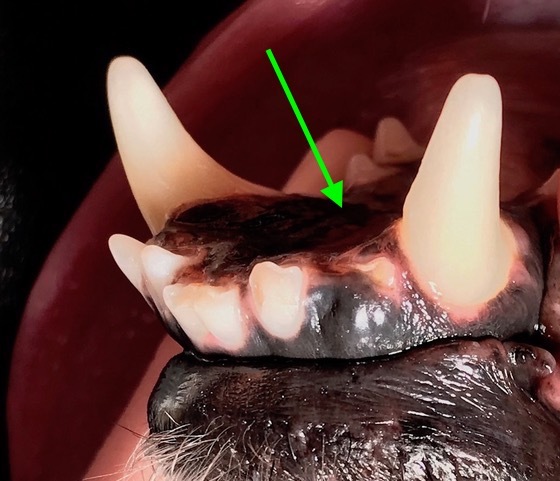

Der hübsche neun Jahre alte schwarze Mischlingsrüde Nando aus Italien wird vorgestellt, da die Besitzerin Zahnstein und einen unangenehmen Geruch aus der Maulhöhle festgestellt hat. Während der Untersuchung werden folgende Befunde erhoben: mittelgradiger Zahnstein an den meisten Zähnen, im Unter- und Oberkiefer je ein abgebrochener Schneidezahn (Abb. 1 und 2) und eine große „Zahnlücke“ im Unterkiefer rechts (Abb. 3). Hier scheinen die drei letzten Backenzähne zu fehlen. Nando ist ein sportlicher und schlanker Hund. Sein Herz schlägt regelmäßig und ohne Nebengeräusche. Dennoch untersuchen wir vor der Operation sein Blut, um mögliche Anästhesierisiken weitgehend ausschließen zu können. Wenige Tage später werden Nandos Zähne in Narkose sorgfältig von Zahnstein befreit und anschließend poliert. Von den beiden abgebrochenen Schneidezähnen und dem Bereich der vermeintlichen Zahnlücke im Unterkiefer werden Röntgenbilder angefertigt. Die Kronen der beiden Schneidezähne sind so tief abgebrochen, dass die Pulpahöhle offen liegt (Abb. 4). Im Bereich der „Zahnlücke“ zeigt das Röntgenbild Wurzelanteile nicht vollständig vorhandener oder vielleicht auch nicht vollständig ausgebildeter Zähne (Abb. 5).